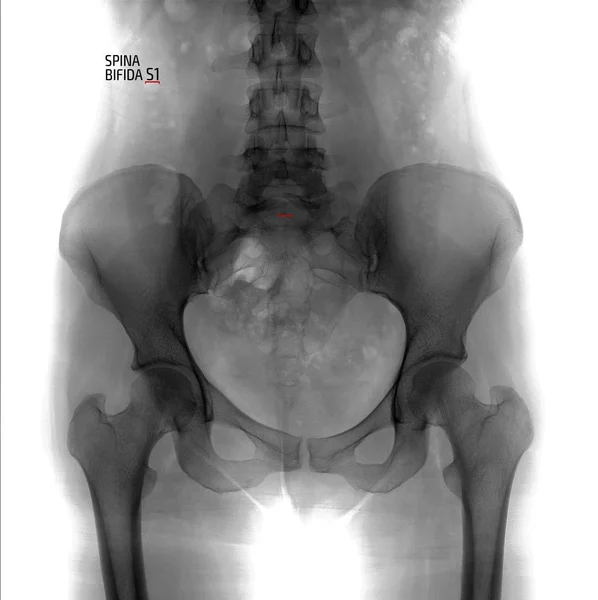

Спина Бифида Фото Рентгена

Спина бифида чаще всего возникает в пояснично-крестцовом отделе на уровне s1-s2 . Клинические проявления заболевания обусловлены степенью выраженности врожденного дефекта .